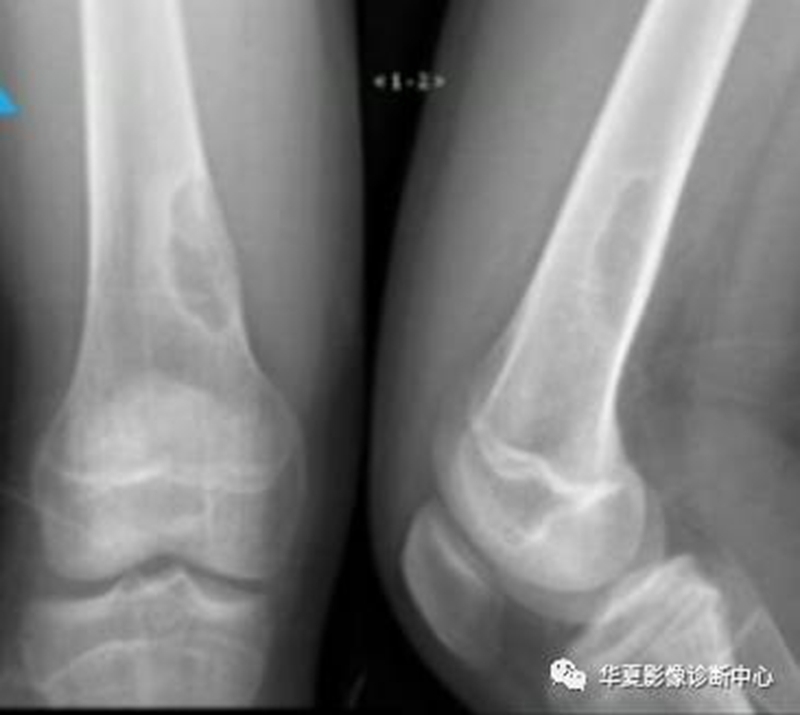

左为亚急性化脓性骨髓炎,右为骨肉瘤